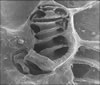

1-İç kulağın bir kısmıdır. Salyangoz kabuğu biçiminde iki buçuk dönüş yapan borusal yapıdır.

2-İç kulakta salyongozda bulunan yapıdır.

Örneğin iç kulakta bulunur. Ses dalgalarının iletimini sağlar.